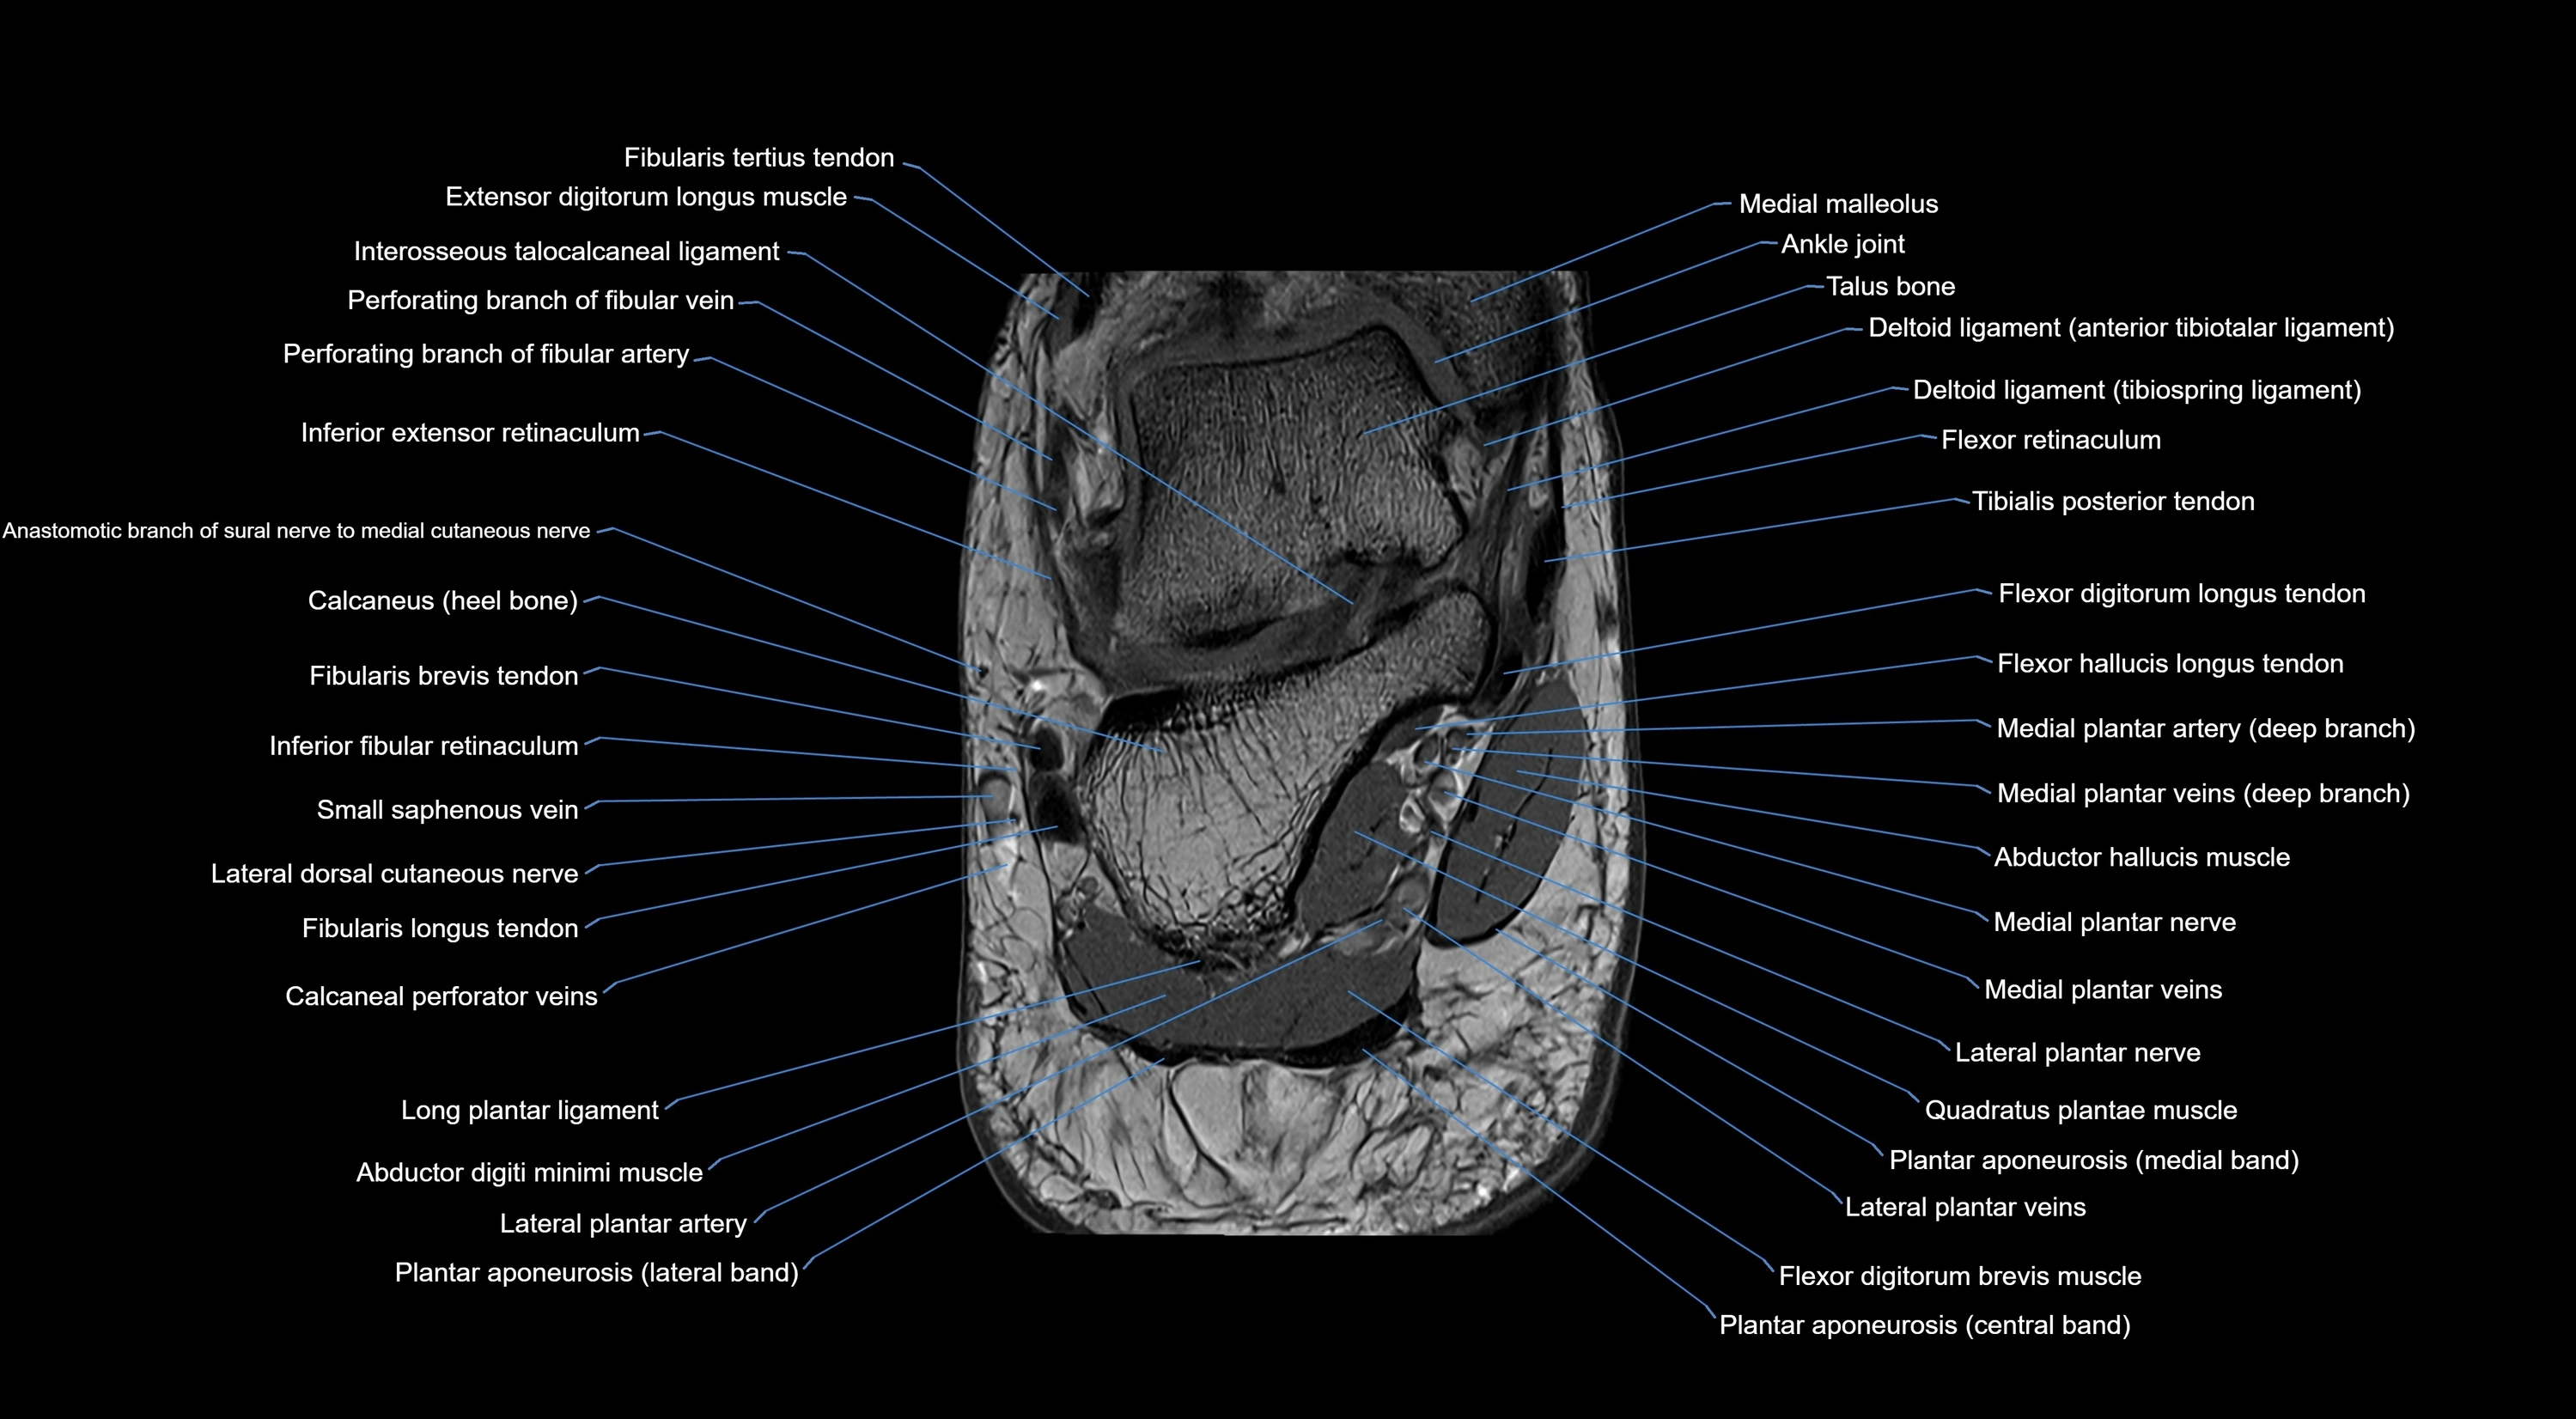

MRI image